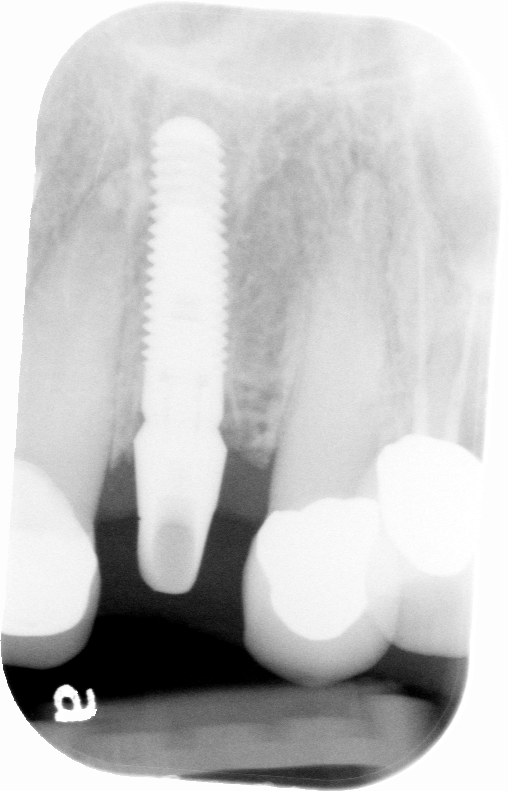

Results: Implant #10 appeared to have initial osseointegration. Radiographs taken at each step exhibit the deterioration of bone over time. Clinical signs of implant failure began 3 weeks after restorative impression. Patient also began experiencing symptoms such as discomfort upon palpation to the site at this time. This case resulted in removal of the implant due to total failure to osseointegrate.

Conclusion: With primarily anterior occlusion, it is possible the late failure of the implant is due to occlusal overload. Another factor that is prevalent in this case is previous medication taken for history of rheumatoid arthritis that can interfere with osseointegration.